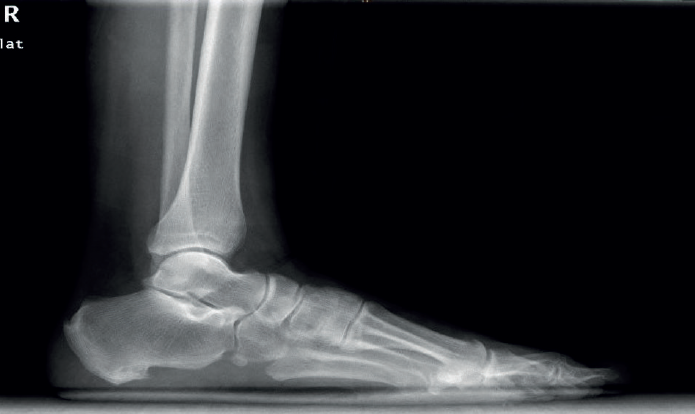

El estudio radiológico se debe realizar de ambas extremidades y en carga, para poder valorar desaxaciones (en varo o valgo) y asimetrías. En la proyección anteroposterior de tobillos se puede observar si existe un arrancamiento de la pared lateral del maléolo peroneal que indica una avulsión del RPS (signo indirecto de luxación conocido como fleck sign). En el perfil podemos valorar la presencia de un OP (Figura 4). La proyección oblicua puede mostrar un tubérculo peroneal hipertrófico a nivel de la pared lateral del calcáneo.